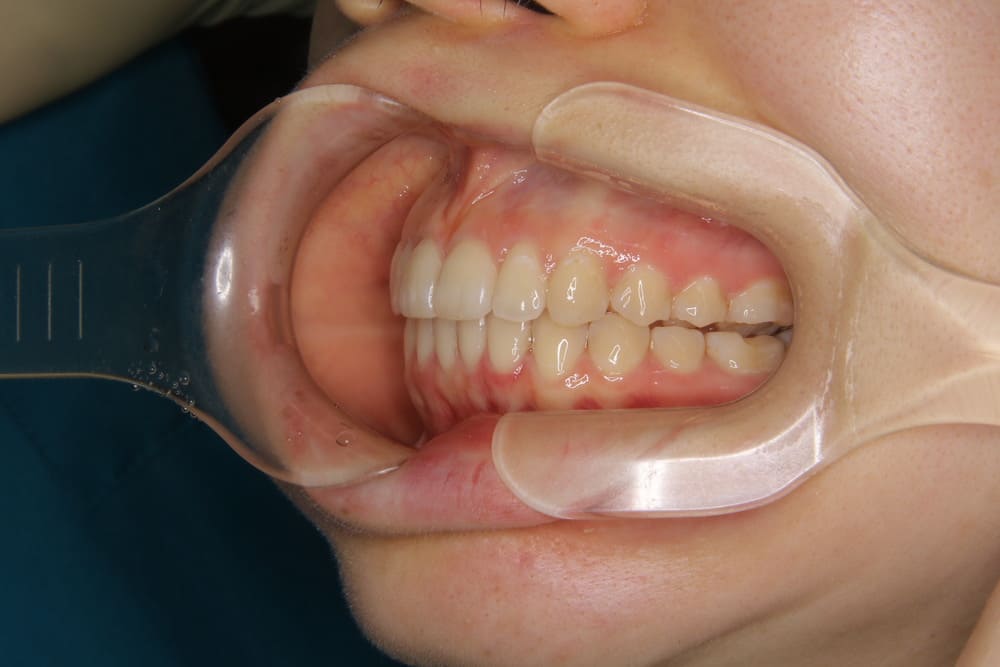

2精密検査

レントゲン撮影、口腔内写真・顔貌の写真撮影、口腔内スキャナー(iTeroなど)による精密な歯型採得など、治療計画の立案に必要なデータを収集します。